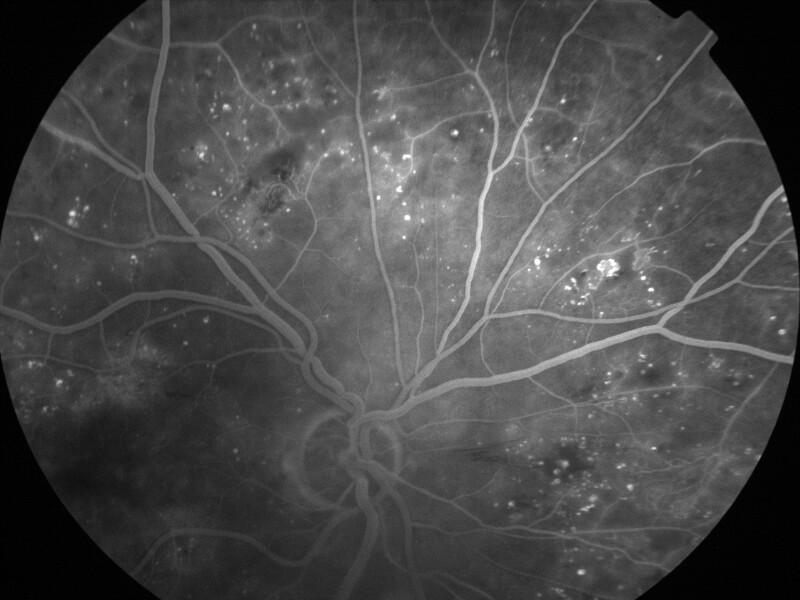

rétinopathie diabétique pré-proliférante

IM000019.jpg